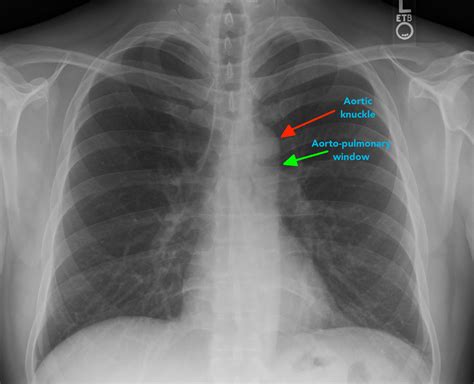

Interpreting Abcde Chest X Ray results requires expertise in radiology. The images are reviewed by a radiologist who looks for various indicators of health or disease. Some common findings include:

Radiologists use a systematic approach to interpret the images, often following the ABCDE mnemonic:

Airways Bones Cardiac Silhouette Diaphragm Everything Else

Examine the trachea and bronchi for any abnormalities. Check for fractures or other bone issues. Assess the size and shape of the heart. Evaluate the position and contour of the diaphragm. Look for any other abnormalities, such as lung nodules or pleural effusions.

This method ensures a thorough and systematic review of the chest X-ray images.